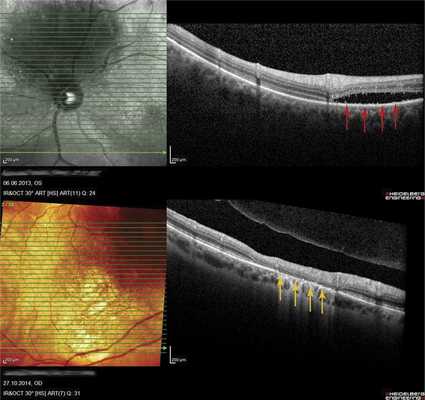

В 8 случаях выявили распространенную зону ОНЭ с дезорганизацией фоторецепторного слоя «на протяжении» от очага (рис. 6, а). В 2 случаях при анамнезе более 15 лет были выявлены зоны разрушения слоя фоторецепторов и наружных слоев сетчатки, соответствующие зонам ранее существовавшей ОНЭ (см. рис. 6, б).

Рис. 6. ОКТ-горизонтальный срез «на протяжении» от ГХ. а - пациентки Х., длительность анамнеза 3,5 года (красными стрелками указана зона ОНЭ); б - пациентки К., длительность анамнеза 15 лет (желтыми стрелками указана зона разрушения слоя фоторецепторов и наружных слоев сетчатки на месте ранее существовавшей ОНЭ, атрофия РПЭ).